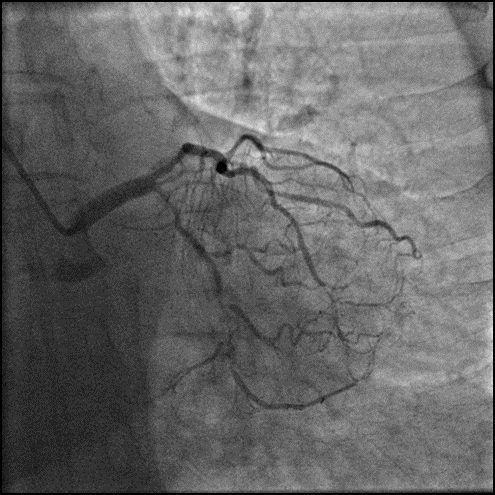

Final Result

Telescope™导引延长导管安心输送长支架-成功输送长支架到位,输送性优异,且无器械剐蹭现象发生。

Telescope™增强支撑力-旋磨后加强支撑,辅助置入支架。

安全挑战钙化病变-重度钙化病变多次旋磨后,无创输送器械。